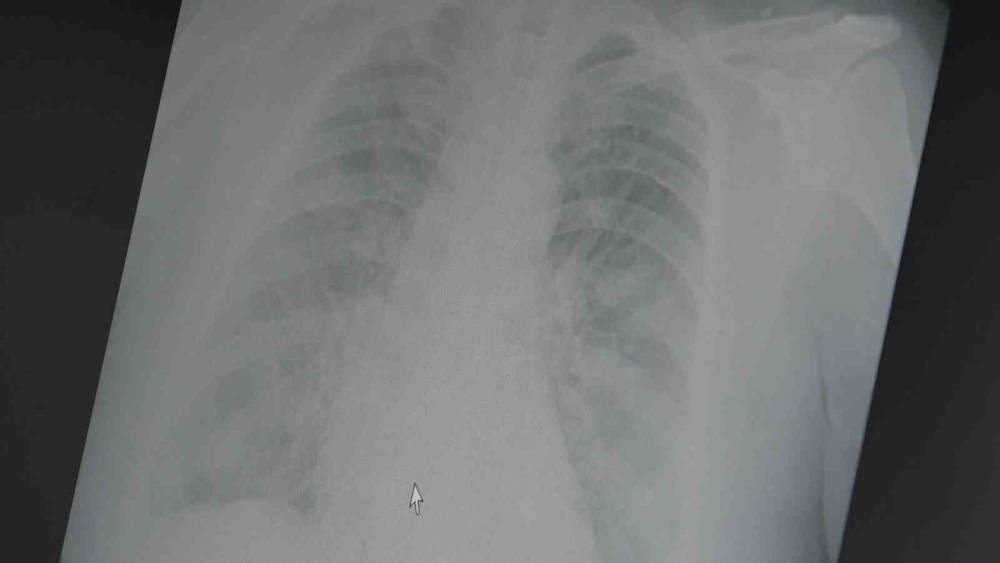

Sezon sonu raporlarına göre bu yıl grip aşıları yetişkinlerde hastalığı önlemede yüzde 25 ila yüzde 30 oranında etkili olduğunu söyleyen Prof. Dr. Şevket Özkaya açıklamalarda bulundu. Bu durumun son 20 yıldaki en düşük etkinlik oranlarından biri olduğunu ifade eden Prof. Dr. Özkaya, erken hakim olan yeni suşun aşının içeriğiyle iyi eşleşmemesinin yoğun grip vakalarına yol açtığını vurguladı.

Yeni suşun A H3N2 tipi olduğunu ve kolay yayıldığını belirten Prof. Dr. Özkaya, "Her ne kadar grip aşılarının koruyucu etkinliği azalmış olsa da, ciddi hastalık ve ölümleri önlemede aşının önemi sürüyor. Grip aşısı yaptırmak hâlâ değerli" dedi.

Prof. Dr. Özkaya, pandemi sonrası grip aşılarının etkinliğinin genel olarak azaldığını ve düşük aşılama oranlarının da etkili olduğunu belirterek, önümüzdeki mevsim için yeni suşları kapsayan aşıların piyasaya çıkmasını beklediklerini sözlerine ekledi.